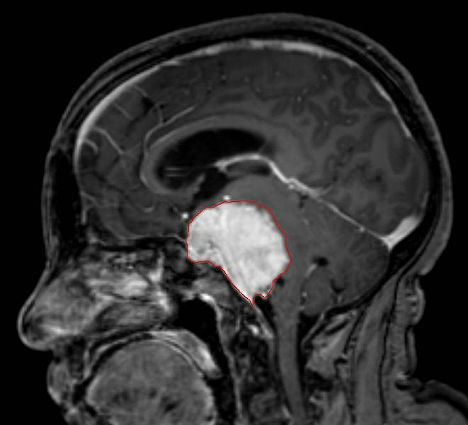

8. 细菌治疗癌症

细菌治疗癌症

在癌症治疗中,一种名为“产孢梭菌”的细菌可以用来输送药物,因为它具有直接命中肿瘤的功能。英国诺丁汉大学科学家尼吉尔-明顿教授发现,“产孢梭菌”只能生长于缺氧的环境中,如肿瘤的中心。当治疗癌症的药物注入到肿瘤中时,这种细菌可以帮助药物直接命中肿瘤细胞,而不会影响健康的组织。研究人员希望,到2013年将这种细菌治疗手段投入临床试验。